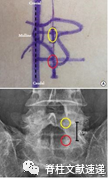

图注:1)多裂肌三角;2)肌肉与椎板之间的间隙(Son’s space)